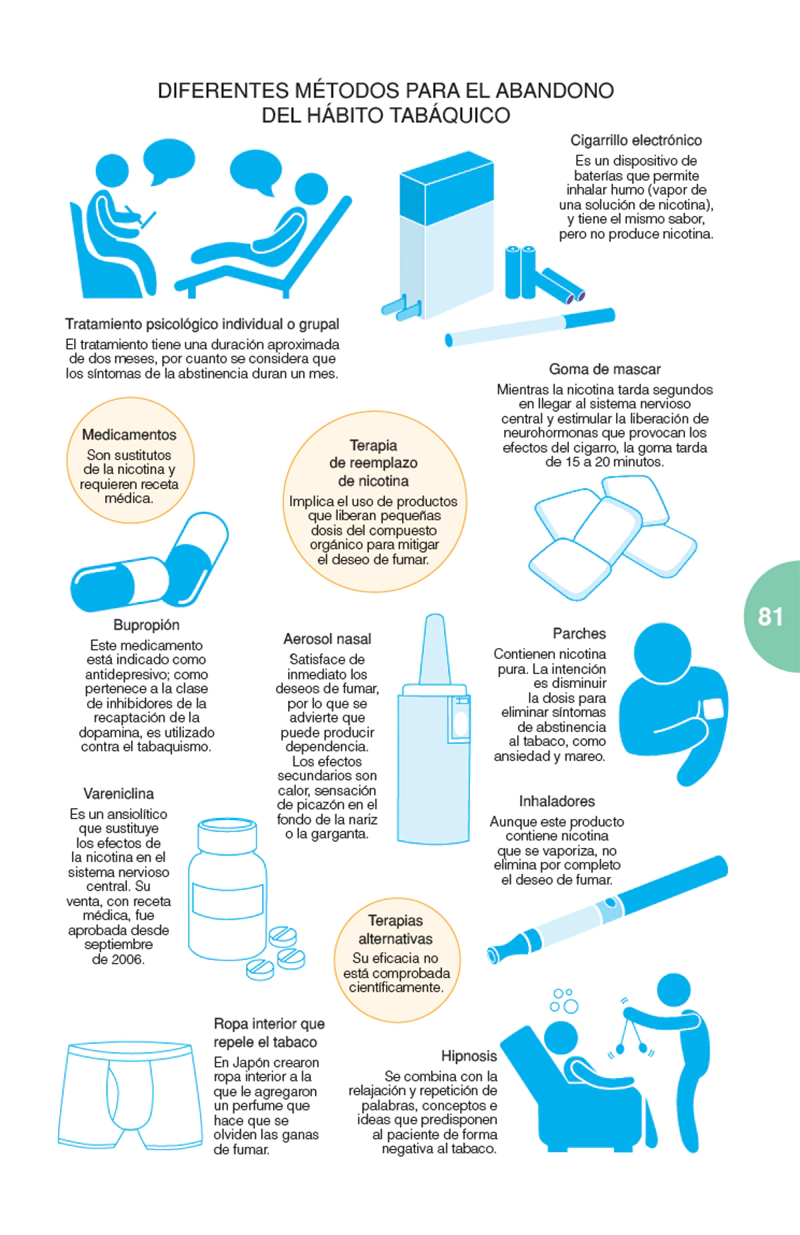

Un libro de la extensión de este no puede explicarlo todo sobre el tema. Pero sí aporta una cantidad más que suficiente de información para que tanto el profesional, como el paciente puedan encontrar en él todo aquello que constituye el núcleo fundamental de conocimientos sobre la enfermedad, además de un gran acopio de materiales complementarios, tanto de tipo ilustrativo como, sobre todo, práctico, que servirán eficientemente para conocer en su globalidad qué es la EPOC, cómo tratarla y la manera más adecuada para que el paciente pueda hacerle frente.